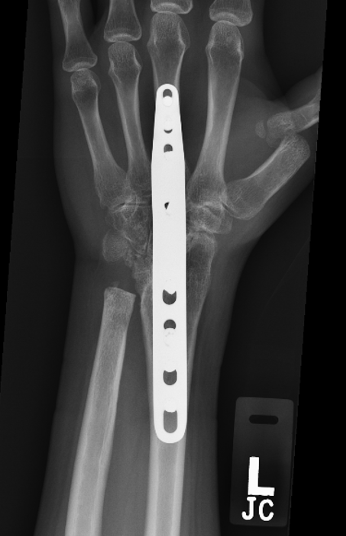

After your hand and wrist has been examined, an X-ray usually determines the degree of damage to the wrist. However, as is often the case, the findings on the X-ray may not correlate with the findings on examination. Some patients may have severe arthritis on their X-ray, yet have very mild symptoms.

X-rays normally show a gap between the bones, as the bones are lined with smooth cartilage, which doesn’t show up on an X-ray. If the cartilage is reduced or absent, the gap between the bones is also reduced, and the ends of bones rub against each other. The body tries to react by making more bone at the edges of the joint. Within the wrist joint, inflammation may develop and this may be painful.

Fusion operations: Fusion is the term given whereby the joint is removed and the bones either side are pinned and held together, so that the bones heal as one piece. The wrist can be partially or fully fused. These operations sacrifice movement of the wrist for pain relief. This is usually the most reliable and predictable treatment for intractable wrist arthritis with up to 85% satisfaction.